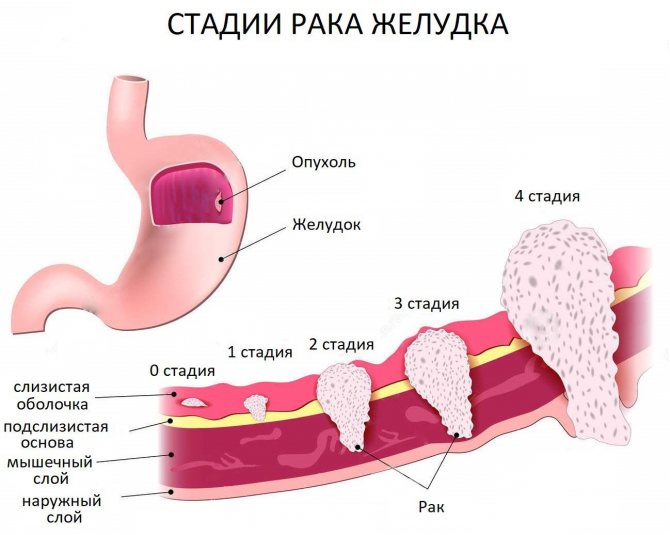

Рак желудка — онкологическое заболевание, при котором злокачественная опухоль поражает стенки желудка. Новообразование формируется в результате метаплазии железистых клеток слизистой оболочки органа. По мере своего роста оно проникает в подслизистый, мышечный, серозный слои, может распространяться на поджелудочную железу, 12-перстную кишку, метастазировать в легкие, печень и лимфатические узлы. Прогноз зависит от скорости роста и степени распространения опухоли.